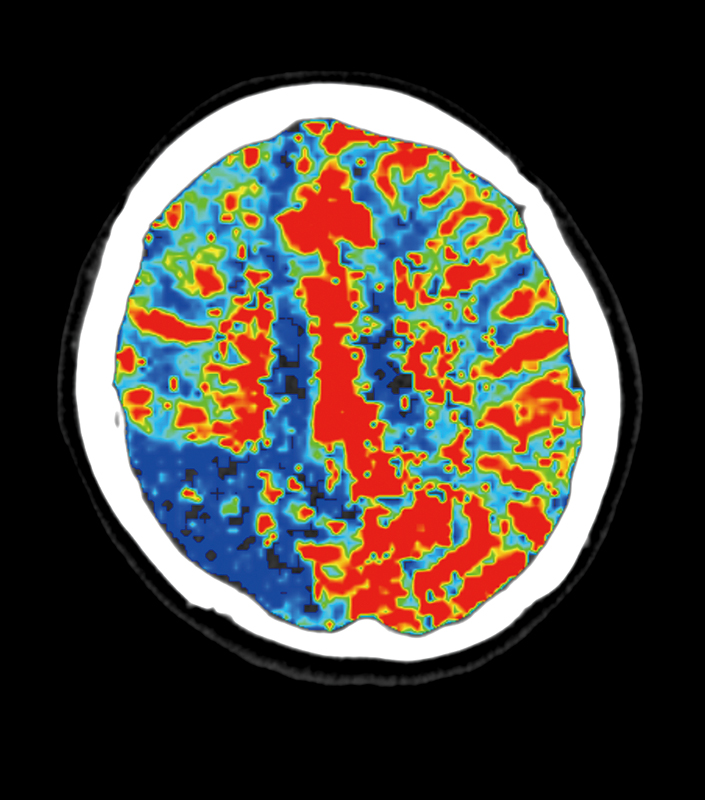

CLINICAL IMAGES